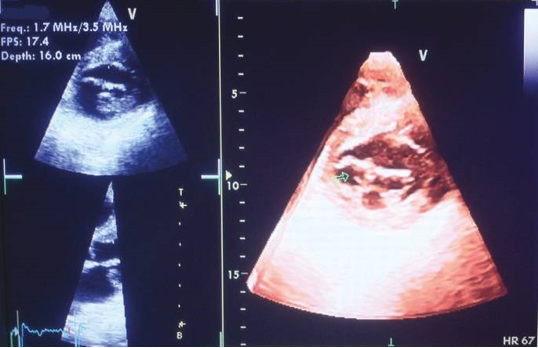

Three-Dimensional Echocardiography

The concept of three-dimensional (3D) echocardiography began to evolve during the 1960s, and the first reports of 3D scans of the heart were documented in 1974. [48] Initially, 3D echocardiograms were obtained using a technique called reconstruction. [47], [48], [49], [50], [51], [52], [53], [54], [55], [56], [57] This technique involved acquiring ECG-gated images from various transducer positions with precise locations. Each image was then placed in its appropriate three-dimensional spatial position within the cardiac cycle using specialized software programs. Through specific image processing techniques, the structure could be reconstructed as a 3D object, allowing for the visualization of surfaces and volumes.

Advancements in transthoracic transducers have made it possible to obtain real-time or near real-time 3D volume data sets. The development of more sophisticated transthoracic transducers has facilitated the acquisition of 3D images in a dynamic and immediate manner, enhancing the clinical utility of 3D echocardiography.

The field of 3D echocardiography has experienced rapid advancements, leading to the availability of various types of real-time 3D imaging techniques. Modern real-time 3D systems employ matrix array transducers equipped with 3000-4000 elements, allowing for detailed and high-resolution imaging.

The ability of 3D echocardiography to depict cardiac structures in close approximation to their real forms has proven to be particularly beneficial in the evaluation of complex congenital heart disease (see [Figure 4]). This imaging modality provides clinicians with valuable insights into the intricate anatomical features and spatial relationships within the heart, enhancing the understanding and management of congenital heart conditions.

Real-time 3D echocardiography has demonstrated high accuracy, feasibility, and value in the operating room, as well as in various clinical applications.[49] Its utilization in contrast-enhanced imaging provides several advantages, particularly in improving the quantification of left ventricular volumes. [50] Moreover, the scope of clinical applications for 3D echocardiography is rapidly expanding. However, the most common indications for real-time 3D echocardiography remain quantitative measurements of left ventricular volumes, assessment of regional wall motion abnormalities (RWMA), congenital heart disease, valvular disease (as shown in [Figure 4]), and evaluation of ventricular desynchrony.